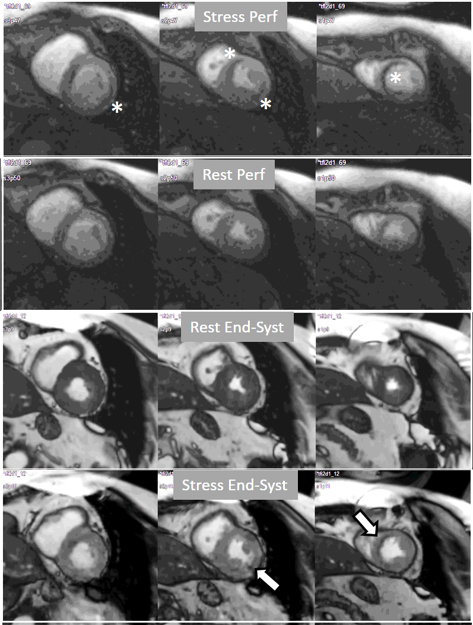

More recently, a new method has been proposed [56] that includes several important solutions contributing to a reliable implementation on the routine workflow of a CMR exam [57]. Firstly, it is based on a dual imaging sequence strategy (Fig. 24), where low-resolution blood pool images used for estimation of the AIF are followed by multi-slice 2D high-resolution myocardial perfusion sequence. The total duration of the scheme is around 500 msec, that allows for the obtention of 3 slices sampled every heart cycle, as long as the heart rate is below 120 b.p.m. AIF extraction from the low-resolution sequence has proven to be reliably obtained automatically [58] (Fig. 25). Second, motion and surface coil intensity correction are applied to both AIF and perfusion images [57, 59]. Third, a process of SI conversion into gadolinium concentration [Gd] units is performed for both sequences [56] (Fig. 26). Fourth, and most important, AIF [Gd] curve and perfusion [Gd] images are inputted into flow mapping step for pixel-wise myocardial flow mapping [57] rendering quantitative values of MBF (in mL/min/g) (Fig. 27). Based on a process of deep learning [60], myocardial segmentation and allocation of flow values are automatically processed (Fig. 28) and integrated into the MRI scanner using the Gadgetron streaming reconstruction software [61, 62]. The final output of the process consists on a bull’s-eye plot of color-encoded MBF values on the LV 16-segment model, and the listed numerical values of absolute flow at stress and at rest and, also, the derived MPR, each of them calculated for the endo- and epicardial halves of the segment (Fig. 29). The presence of inducible perfusion defects is thus detected not only visually on the perfusion color map, but also quantitatively estimated by the absolute values of stress MBF and the corresponding MPR of the involved myocardial segments (Fig. 30). Of note, in case of a suboptimal effect of the vasodilator agent, a lack of increase in stress MFB and MPR values is observed, leading to a potentially false positive diagnosis, in contrast with the visual assessment of perfusion, which, in this case, as stated above, would not show induced defects, with the potential for a false negative.

Fig. 30.QP study in a patient with an inducible defect. A defect at the inferior basal region is detected in the conventional stress perfusion sequence (white arrow). QP maps from the corresponding basal segments show transmural intense reduction of the stress MBF and MPR at the inferior segment (red arrow and asterisks), with less severe involvement of the infero-lateral one (blue arrow and asterisks). Observe the reduced stress MBF in comparison with the rest value of the inferior segment, with a resultant MPR value significantly decreased, inverted actually (0.93), indicating coronary steal phenomenon and, in accordance, probably severe inducible ischemia of the region.